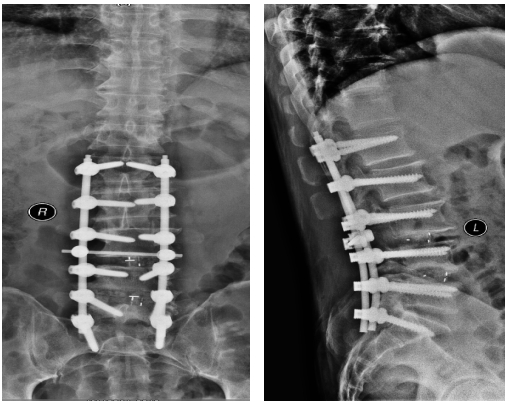

天时地利人和,一切准备就绪,2019年1月7日,骨一科对王师傅成功实施了“经后路腰椎侧弯畸形矫形+钉棒螺钉内固定+腰3/4、4/5椎管切开减压+腰4/5 、骶1双侧神经根探查松解+椎间盘切除+椎间、椎体后侧植骨融合术”,手术历时5小时45分。术后患者恢复良好,腰部侧弯、腰痛等问题一去不复返。

术后影像